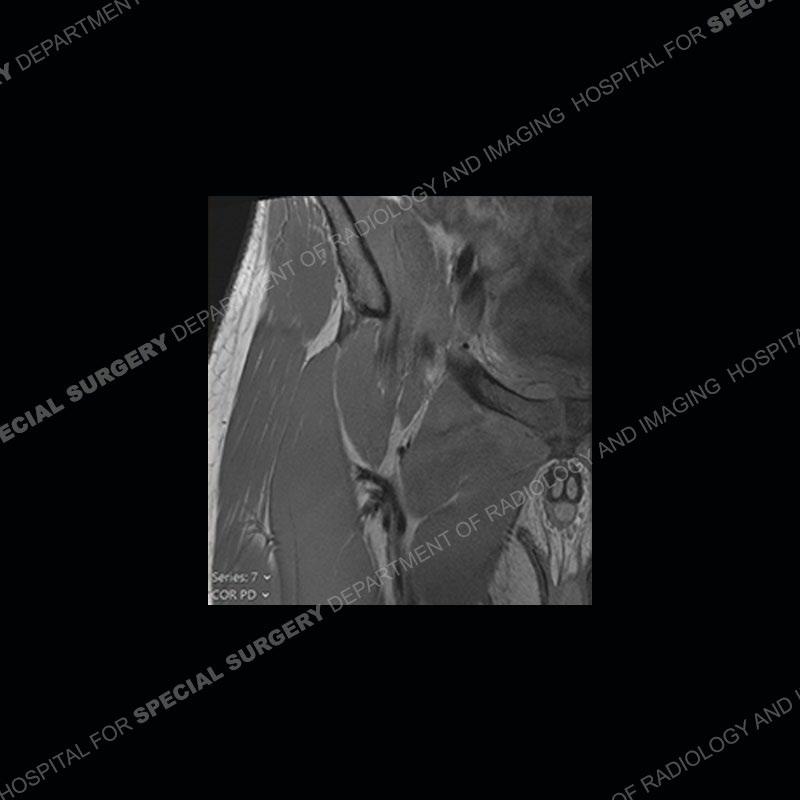

Radiographs did not demonstrate any clear abnormality. The MRI shows markedly abnormal signal of the right superior pubic ramus and abnormal signal/”mass” extending into the adjacent soft tissue. The inferior articular surface of the ramus showed what was thought to be bony destruction. CT examination shows a destructive process of the right superior pubic ramus.

Subsequent MRI in a very short time interval shows markedly increased abnormality of the ramus and increased edema and “mass” of the soft tissue. Post contrast imaging shows multiple, rim enhancing collections of the soft tissue and similar albeit less conspicuous enhancing collection of the ramus.

Diagnosis: Osteomyelitis and Soft Tissue Abscess